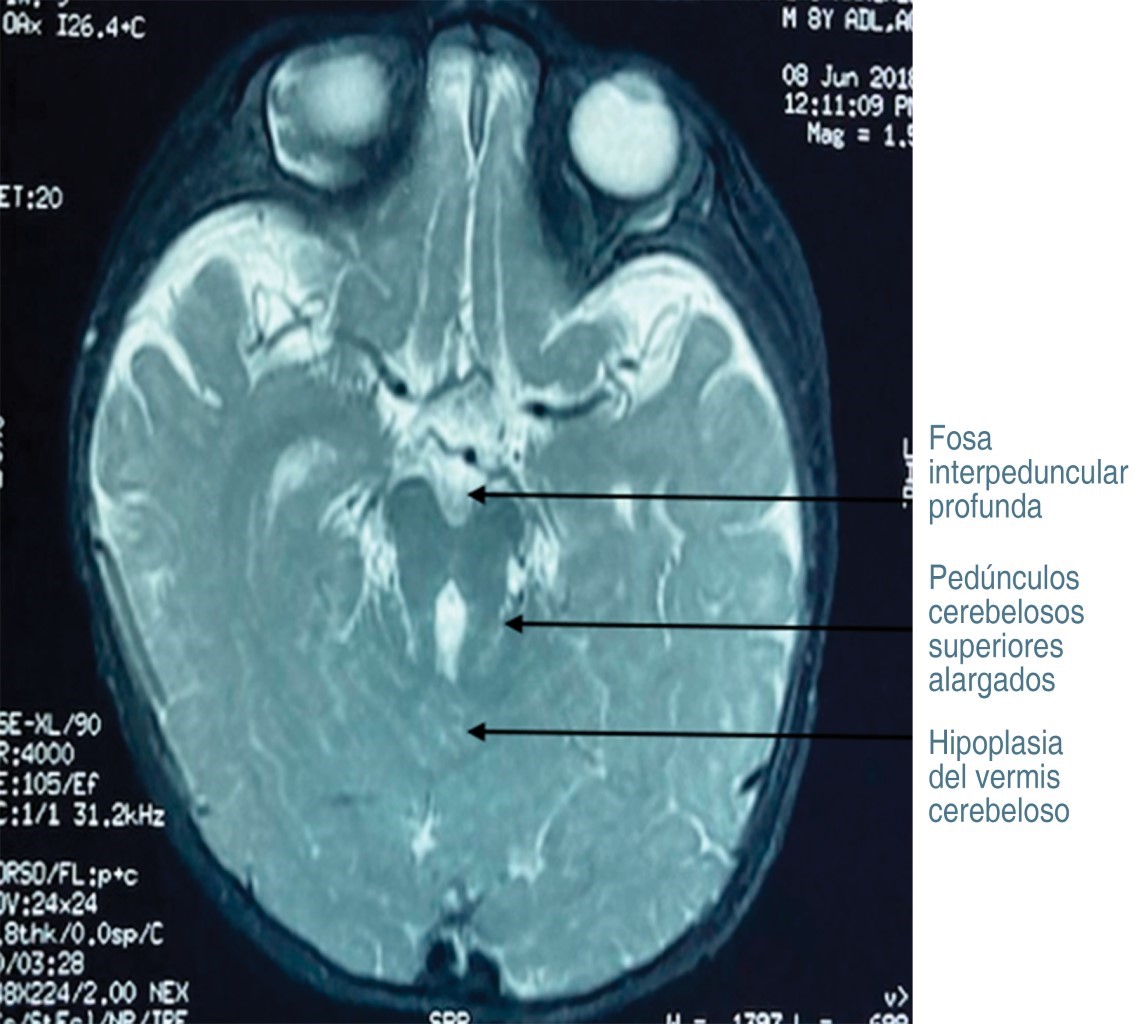

Introduction: Joubert syndrome (JS) is an autosomal recessive congenital ciliopathy, which has been associated with a mutation in the TMEM67 gene. JS is characterized by delayed psychomotor development, ocular alterations, as well as renal, skeletal, and hepatic manifestations. Magnetic resonance imaging (MRI) identifies the pathognomonic alteration, which is a malformation in the cerebellum and brainstem, with a characteristic image of the "molar tooth sign" (MTS). Objective: to describe the clinical picture of a pediatric SJ patient in whom variants in the TMEM67 gene were detected. Case report: three-year-old male with delayed psychomotor development, hypotonia, isometropic amblyopia, strabismic amblyopia, and downward vertical nystagmus. In the MRI, the MTS was observed since the superior cerebellar peduncles were found to be elongated. By genetics, through whole exome sequencing, two variants in the heterozygous state of the TMEM67 gene were found. Conclusions: children with delayed psychomotor development and nystagmus should undergo a comprehensive ocular, neuroimaging, and genetic examination to identify the diagnosis of JS.

Figure 1